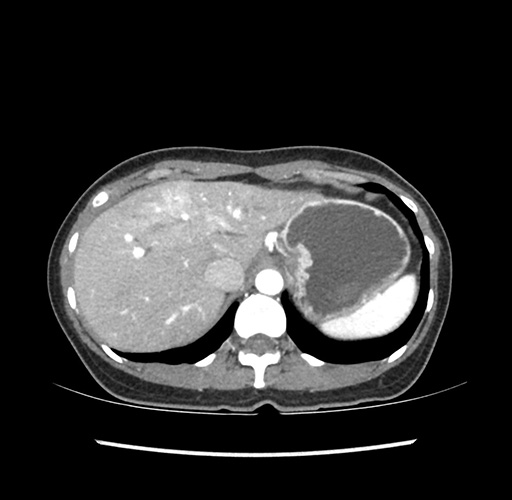

Imaging Analysis

Look through the patient's CT scan to identify any areas of concern for the necessary procedure.

Based on your CT findings, which issue(s) would give reason for "planned slowing down moment(s)" in this case?

Considering a standard left lateral sectionectomy procedure, what step(s) of the operation would you do differently in this case ?